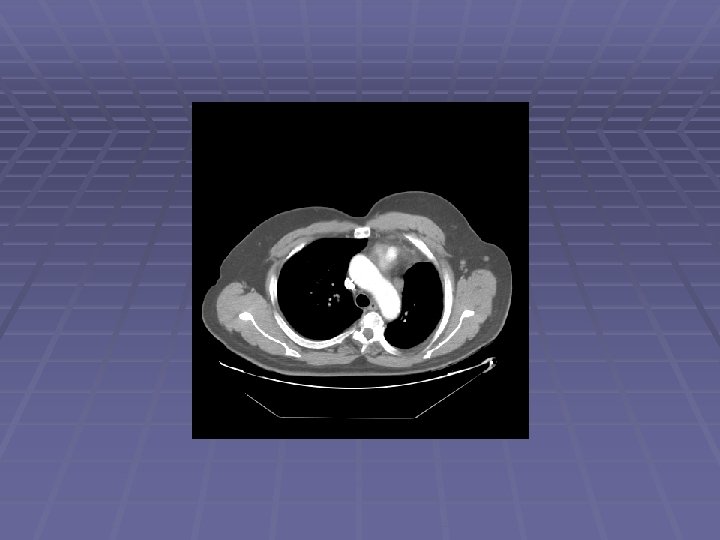

Patient CE 69 y. o. man with h/o non-small cell lung cancer s/p LUL resection in 2006 who is referred after a chest CT showed new mediastinal lymphadenopathy EUS/FNA scheduled to evaluate for recurrent disease

Endosonographic Evaluation EUS Suspicious lymph nodes in the aortopulmonary window, sized 6 -11 mm Suspicious lymph nodes in the subcarinal space, sized 6 -12 mm FNA performed